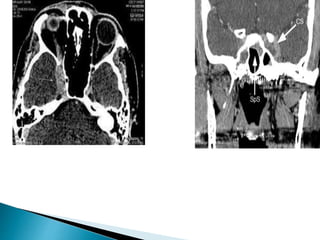

2) Contrast enhanced CT

๏ฝ Slice thickness 3mm or less

๏ฝ Shows enlargement and expansion of

cavernous sinus cavity with flatening or

convexity of lateral wall

๏ฝ Multiple or single filling defect with

enhancing CS.

๏ฝ Exopthalmos, soft tissue edema

๏ฝ Dilation of superior ophthalmic vein

2) Contrast enhancedCT ๏ฝ Slice thickness 3mm or less ๏ฝ Shows enlargement and expansion of cavernous sinus cavity with flatening or convexity of lateral wall ๏ฝ Multiple or single filling defect with enhancing CS. ๏ฝ Exopthalmos, soft tissue edema ๏ฝ Dilation of superior ophthalmic vein